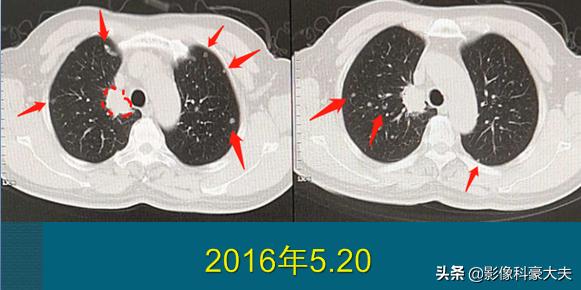

这位病人67岁,男性,因为咳嗽、胸痛做肺部CT,右上肺癌3.1cm,边缘有毛刺。因为肿瘤贴近胸膜,癌细胞沿着胸膜脉管系统(主要是淋巴系统)快速播散,像种子一样在双肺生根发芽,长出100多个转移瘤,还有胸椎、肋骨的多发骨转移,已经无法手术。

后来穿刺证实为低分化肺腺癌,基因检测阳性。他采用靶向治疗为主的综合治疗,吃了两年吉非替尼,定期服用双膦酸盐药物控制骨转移,辅助应用一下调理免疫的药物,从今年开始更换新的靶向药物,目前控制比较理想:

晚期癌症病人的治疗费用不算低,很多时候是用钱续命。有的人有药,买不起;有的人有钱,没有药了(靶向药存在耐药期,长短不一,幸运的人可以5年以上不耐药,不幸的可能只维持几个月就需要换药),这方面还需要更多的研发,找到更多的靶点或者新的方法,让更多的病人有药可用!